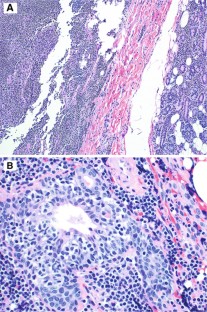

Fig. 1